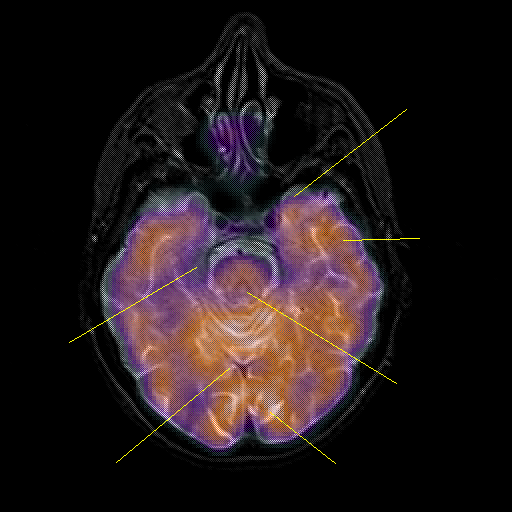

overlay : Slice 18

Slice 18

Pointers

Labeled